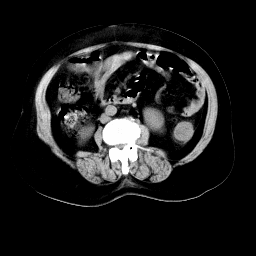

以下是引用arven在2008-11-9 10:13:00的发言:[br]肠壁增厚,形态较规则,支持降结肠炎症改变